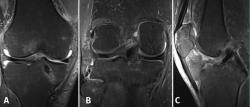

Figure 6. Magnetic resonance imaging views showing correct positioning of both menisci, without evidence of meniscus extrusion (A); consolidation of the bone fragment of the reinserted medial root (B); and intact and correctly positioned anterior cruciate ligament plasty (C).

Four months after the operation, control MRI revealed correct positioning of both menisci, with no evidence of meniscus extrusion (Figure 6A), and with consolidation of the reinserted fragment (Figure 6B). The ACL plasty was seen to be intact and correctly positioned (Figure 6C). At physical examination, the joint balance of the knee comprised a 5º defect for complete extension, with a passive flexion range of 120º and an active range of 100º, with correct anteroposterior and mediolateral stability.